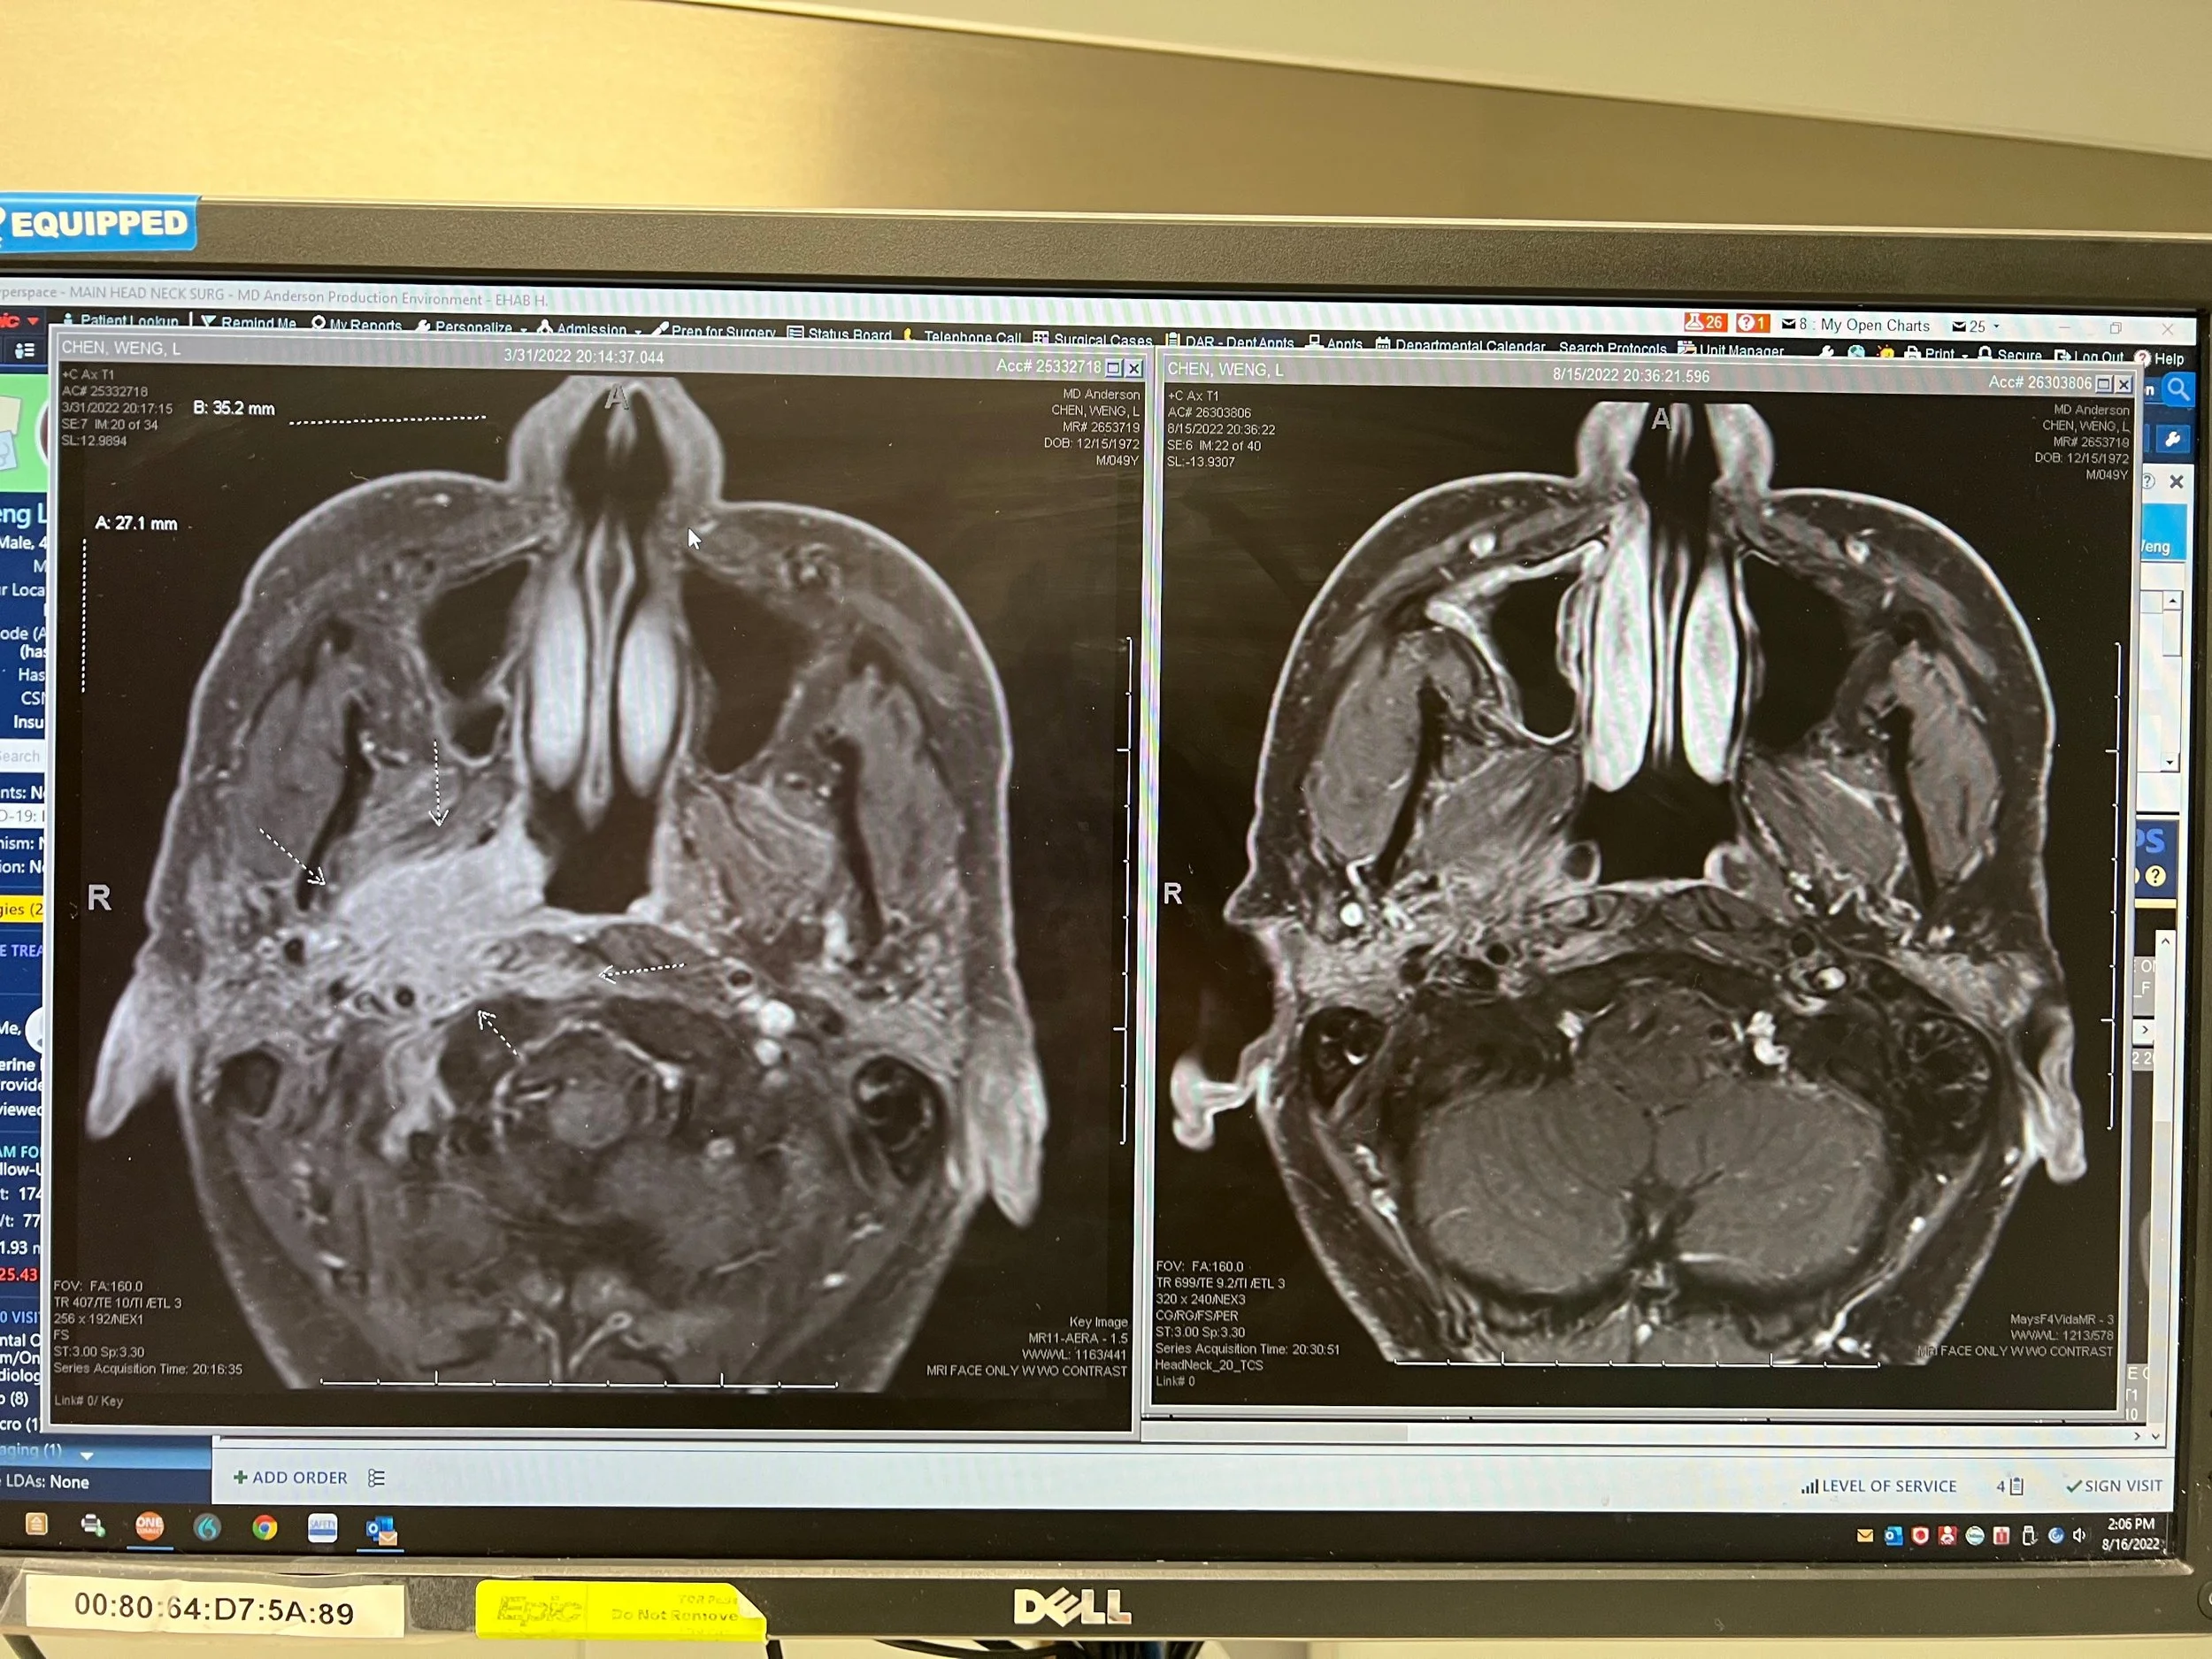

MRI scans - pre-treatment (31 March) on the left; current (15 Aug) on the right. The current scans shows that the two sides of my head are very similar. The lighter/whiter area on the pre-treatment scan was the cancer

Wednesday was an important day, as we were scheduled to see Dr. Gillison (medical oncology) and then Dr. Phan (radiation oncology). Dr. Gillison read the MRI similarly to Dr. Hanna, and she estimated a 97-100% response, with the 3% being the unclear part.  According to her note, “He has had an excellent response with one area of slight enhancement that precludes use of "complete response", but could be inflammatory.”